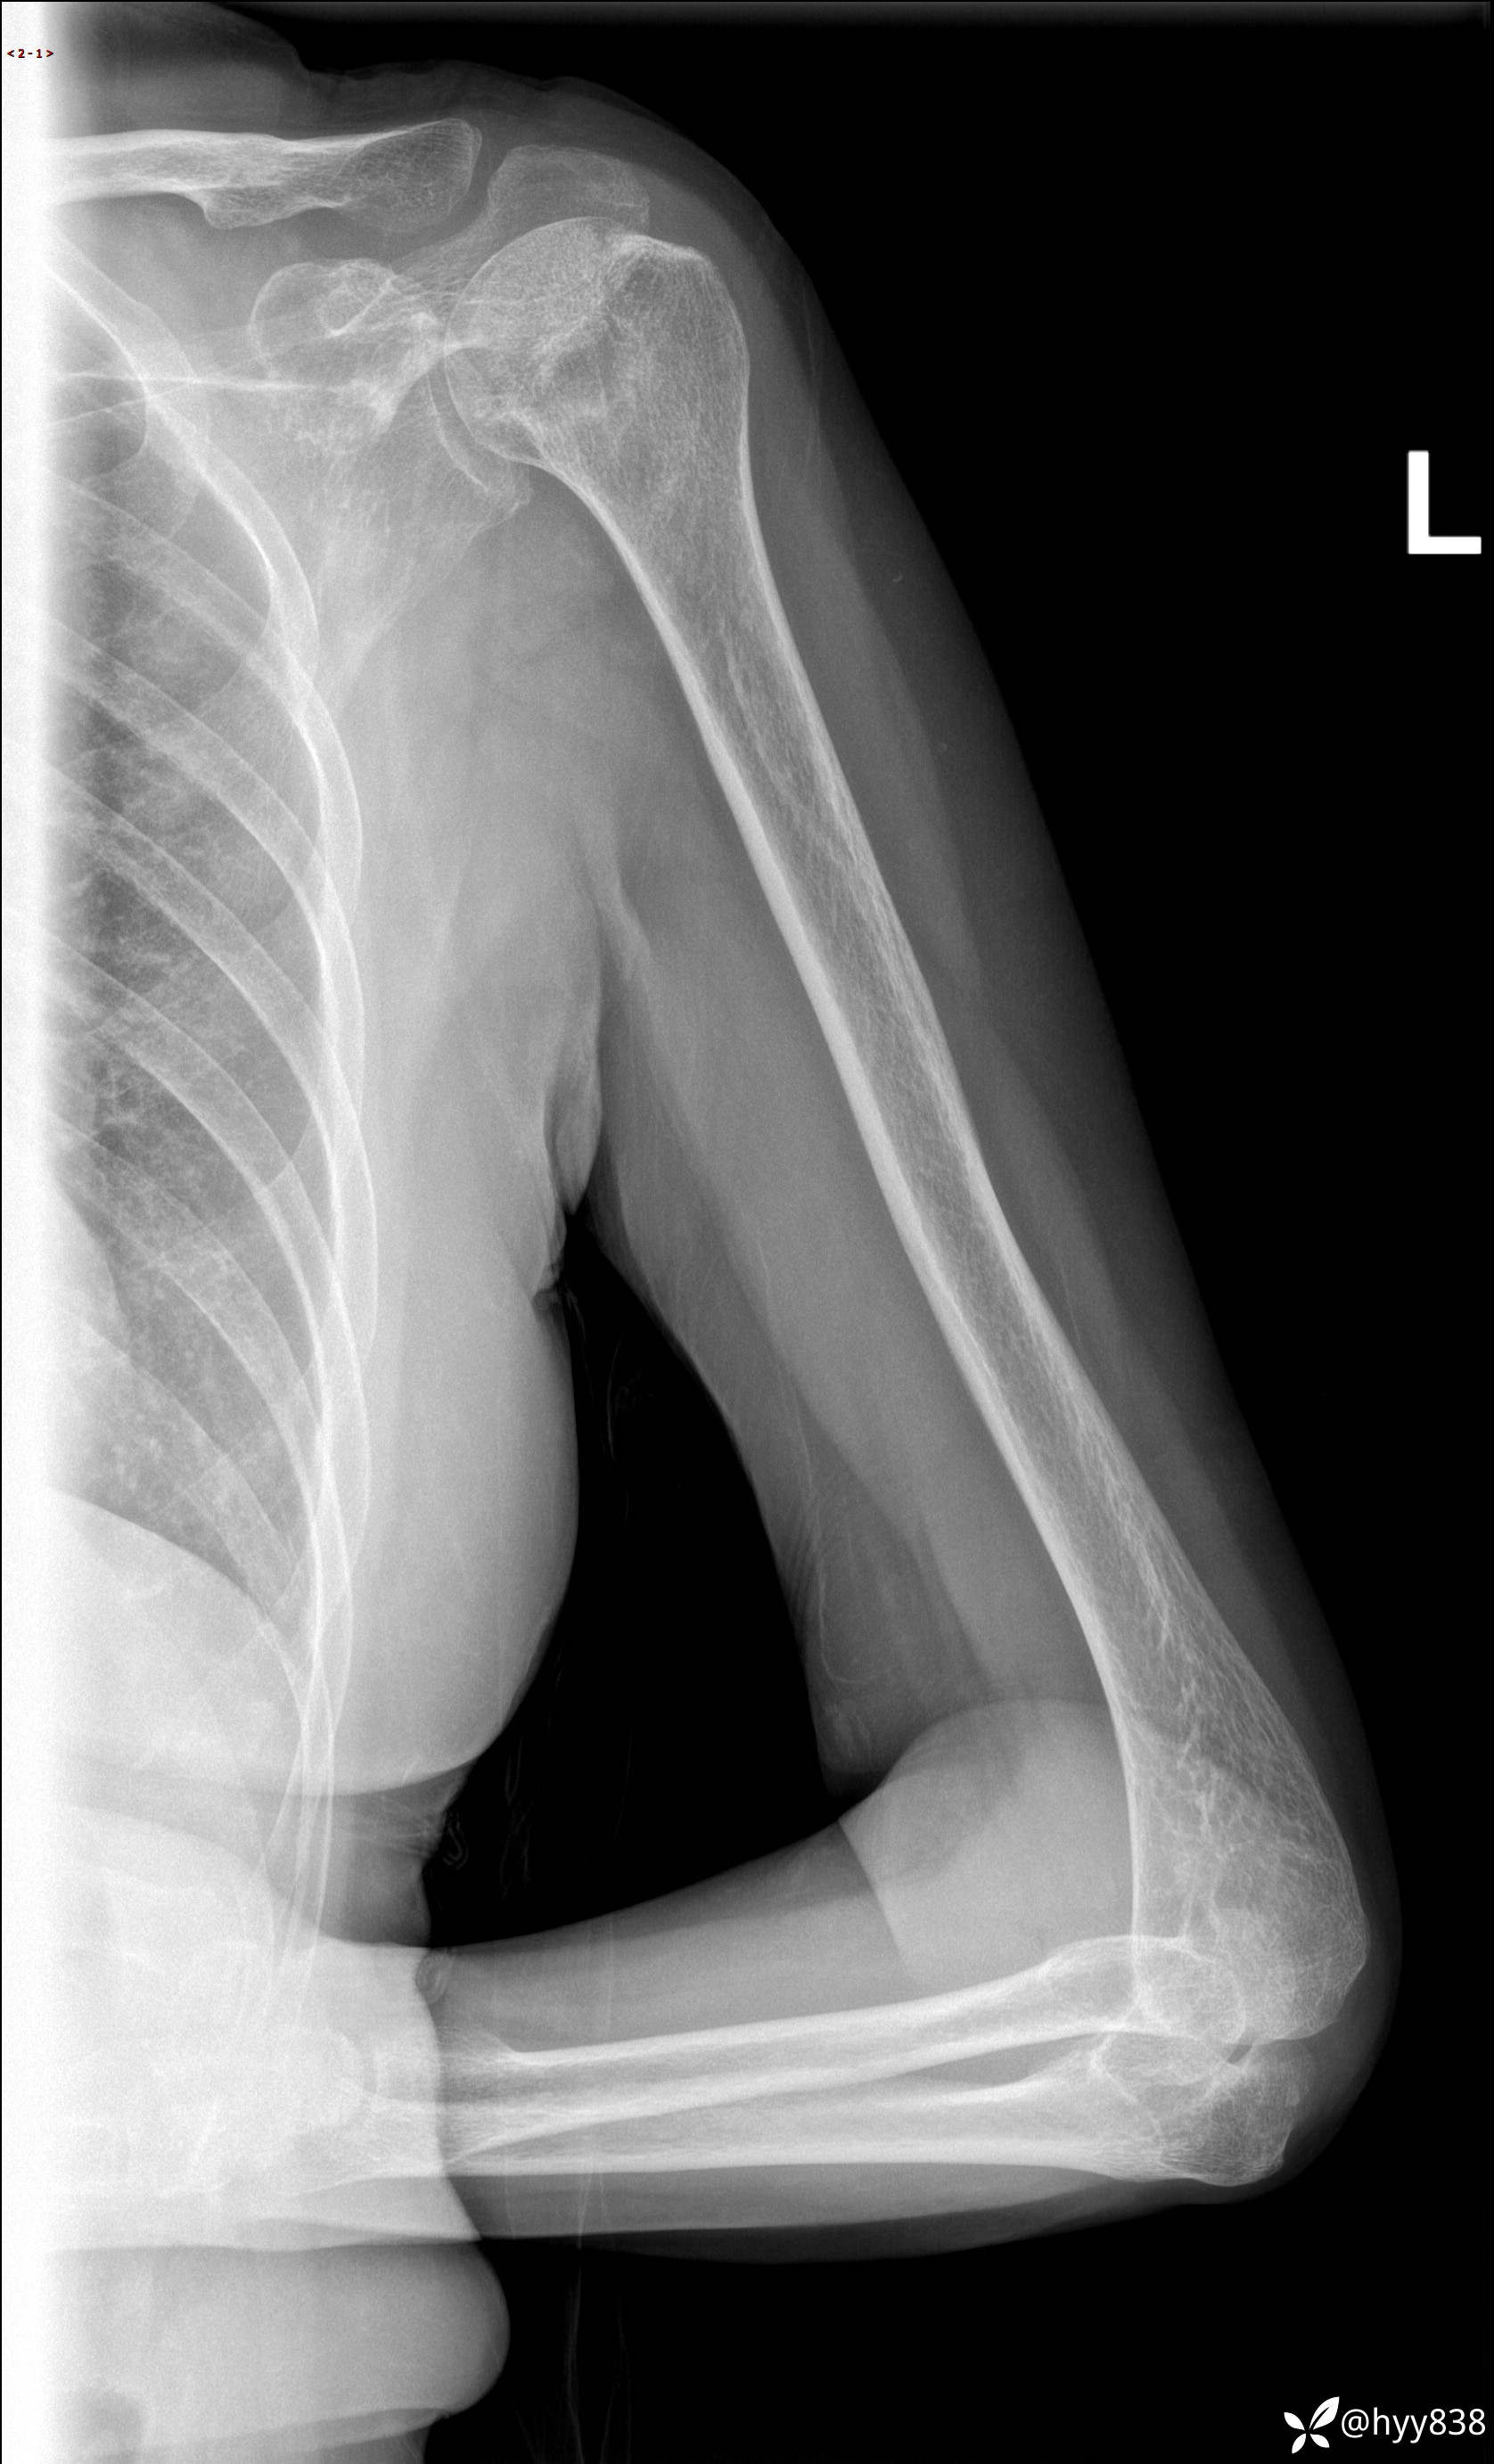

肱骨正侧位片

主诉:发现左侧肱骨头破坏1天。

现病史:患者1月前无明显诱因出现左肩关节疼痛,于2024.07.31就诊于我院骨科门诊完善左肩关节MR:左肱骨头信号异常,肿瘤?建议进一步检查。左肩关节积液。左腋窝淋巴结增大。今为求明确诊断就诊我科,门诊以“骨质破坏”收入我科。 起病以来,精神食欲睡眠尚可,大小便正常,体力体重无明显变化。